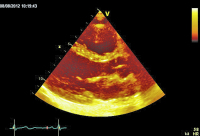

Parasternaler Längsschnitt

Abbildung 2: Parasternaler Längsschnitt mit Farbdoppler: Aorteninsuffizienz mit schmalem Jet (Vena contracta < 0,3 cm, < 25 % des LVOT).